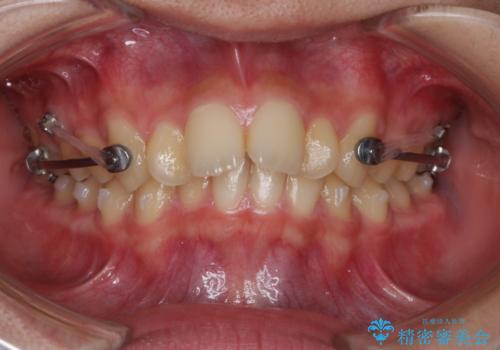

- インビザライン カリエール

よって上顎の歯を抜いて治療をするのではなく、カリエールという器具を使用して下顎を前に引っ張り出しながら上顎を引っ込めるという治療を行うことにしました。